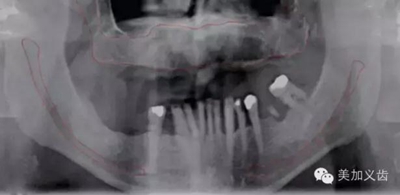

口腔影像學(xué)檢查覆蓋到口腔領(lǐng)域的方方面面,無論是在牙體牙髓科、牙周科、修復(fù)科,還是正畸科,都離不開影像學(xué)檢查,種植領(lǐng)域同樣如此,我們必須準(zhǔn)確的評估缺牙區(qū)的條件,才能放心的開展種植。

常用的口腔影像學(xué)檢查有:根尖片、曲面斷層片及錐形束CT(CBCT),通過三者的結(jié)合,可以準(zhǔn)確的評估缺牙區(qū)骨組織的質(zhì)與量,避開重要的解剖結(jié)構(gòu),從而選擇最適合的植體。

——曲面斷層片

同樣為二維放射線影像,可以獲得如下信息:

·可用骨的高度

·重要解剖結(jié)構(gòu)

·皮質(zhì)骨和松質(zhì)骨的相對密度

·初篩種植位點病變

其優(yōu)點是:能看到的范圍比根尖片要大很多,尤其是拍攝多牙位時,是根尖片無法比擬的。設(shè)備成本相對較低,能開展種植的都能買起,放射計量也比較少。

同時,曲面斷層片也存在缺陷,拍攝后的影像會有放大,或者存在扭曲和變形,此時測量的數(shù)據(jù)是不可靠的。曲面斷層片在拍攝時存在結(jié)構(gòu)重疊現(xiàn)象,因此會出現(xiàn)上頜竇粘膜的假陰性和假陽性病變,這也是其不準(zhǔn)確的地方。

如何通過曲面斷層片測量出相對準(zhǔn)確的數(shù)據(jù)?告訴大家一個很實用的方法,就是利用小剛球作為參照。

將小剛球放到口內(nèi)時拍攝曲面斷層片,拍攝后得到的結(jié)果就是這個樣子的:

5.jpg

因為小剛球的直徑是固定的,通過測量片子上小剛球的直徑,就能算出曲面斷層片的放大率,然后就能算出真實的骨高度了,這是一個很不錯的方法。